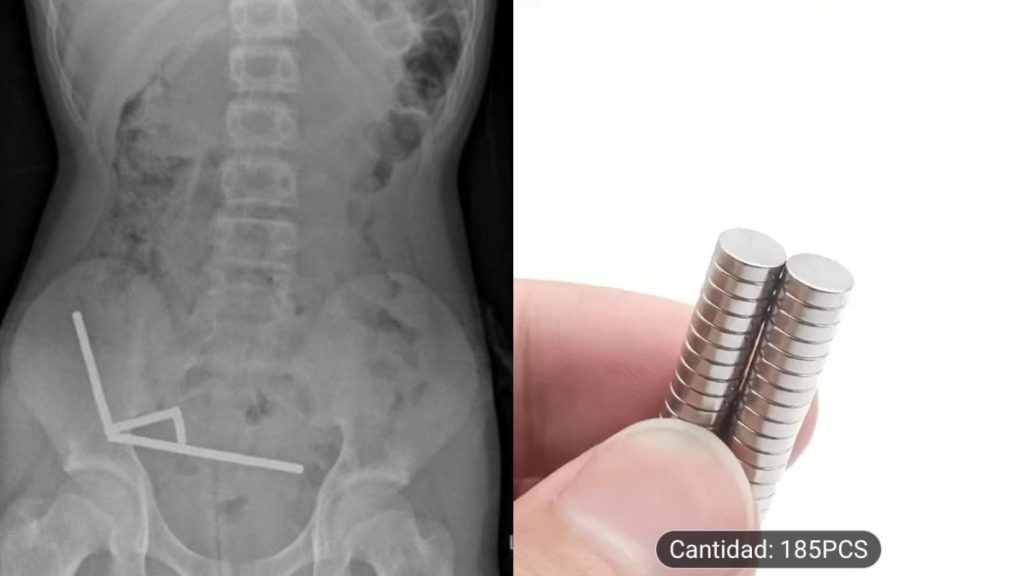

En la consulta, el niño de 13 años confesó que se había tragado entre 80 a 100 imanes de alta potencia (neodimio) de 5x2mm que había comprado por el comercio online Temu.

En el análisis físico, presentaba alta sensibilidad en el cuadrante inferior derecho de su abdomen, lo que fue confirmado por la radiografía abdominal, que reveló “cuatro cadenas lineales de imanes localizadas en el cuadrante inferior derecho del abdomen. Estas parecían ser partes separadas del intestino adheridas entre sí debido a las fuerzas magnéticas”.

En esta línea, en la publicación se detalla que los imanes estaban causando necrosis por presión en el ciego (la primera porción del intestino grueso) y dos áreas del intestino delgado. Por lo anterior, “se realizó una resección ileocólica y dos resecciones en cuña del intestino delgado para recuperar los imanes”.